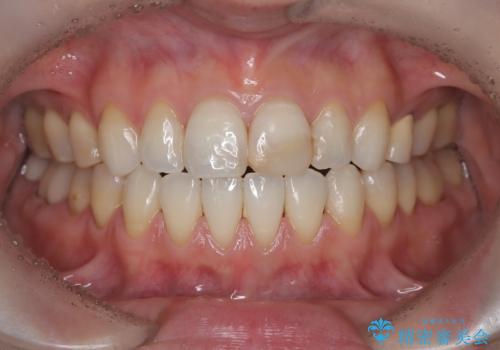

- 「前歯の色が気になる」を主訴に来院された患者さんです。以前他院にて、前歯2本をCR(プラスチック)で治療されていたところが劣化し変色していました。歯の長さも左右で異なっている状態でした。大部分がCR(プラスチック)修復されていたので、オールセラミッククラウンで治療を行いました。

古いCR(プラスチック)とその下の虫歯を除去した後に新しい土台を立てています。適合が良い被せ物を作るために拡大鏡を使用しながら歯を削り、変形のほとんどないシリコンという材料で型取りを行っています。